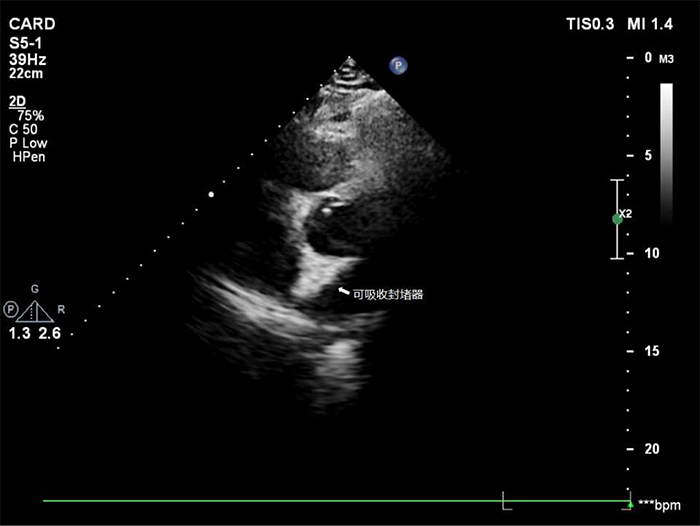

新型可降解封堵器在人体内逐渐降解为二氧化碳和水而被人体吸收,12个月后完全消失,有效的避免了金属封堵器永久存在于体内的一些弊端,为卵圆孔未闭患者带来了新的福音。

据兰大一院心内科介绍,相比传统金属卵圆孔未闭封堵器植入过程中的清晰可视,新型生物可降解卵圆孔未闭封堵器的植入更具难度,在X线下仅可见4个显影点,整个手术在白明教授团队和长海医院心内科秦永文教授的合作下按照预期顺利完成。